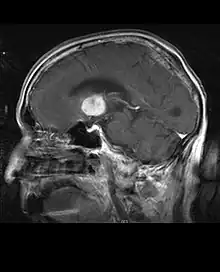

La tomodensitométrie (TDM) et L'imagerie par résonance magnétique (IRM) peuvent détecter efficacement une néoplasie dans le cerveau. L'IRM est plus sensible que la TDM pour identifier les lésions, mais présente des contre- indications pour les patients porteurs de stimulateurs cardiaques, de prothèses incompatibles, de clips métalliques et contre-indications. La TDM reste la méthode de choix pour détecter les calcifications au sein des lésions ou les érosions osseuses de la calotte ou de base du crâne. L'utilisation d' agents de contraste, iodés dans le cas du scanner et paramagnétiques (gadolinium) dans le cas de l'IRM, permet l'acquisition d'informations sur la vascularisation et l'intégrité de la barrière hémato-encéphalique, une meilleure définition de la tumeur tumorale par rapport à l' œdème environnant et à la génération d' hypothèses sur le degré de malignité. L'examen radiologique permet également d'évaluer les effets mécaniques et les modifications importantes des structures cérébrales résultant de la tumeur, telles que l' hydrocéphalie et les hernies, dont les effets peuvent être fatals. Enfin, en préparation à la chirurgie, ce diagnostic peut être utilisé pour déterminer la localisation de la lésion ou l'infiltration de la tumeur dans des zones vitales du cerveau. À cette fin, l'IRM est plus efficace que la tomodensitométrie car elle peut fournir des images en trois dimensions.

Sur-L'IRM montre une tumeur intracrânienne comme une lésion massive qui peut devenir plus luminescente après utilisation du produit de contraste. Cependant, il y a toujours une anomalie de signal dans -L'imagerie par résonance magnétique, qui indique la présence d'une néoplasie ou d'un œdème vasogénique. Habituellement, une luminescence accrue (amélioration du contraste) indique une tumeur d'un grade supérieur de malignité. Un anneau de contraste est caractéristique du glioblastome, avec la partie luminescente correspondant à la partie vitale de la tumeur maligne, et la plus foncée - zone hypointense correspondant à une nécrose tissulaire.

En règle générale, les patients atteints d'astrocytome anaplasique présentent des crises d'épilepsie, des déficits neurologiques focaux, des maux de tête et des changements de personnalité. L'âge moyen des patients est de 45 ans. L'imagerie par résonance magnétique montre généralement une lésion massive avec un signal de contraste accru, qui peut aussi être plus faible. Le diagnostic repose sur l'examen histologique de la lésion par biopsie ou résection chirurgicale.

L'IRM montre généralement une lésion de contraste massive impliquant le cervelet. Comme mentionné ci-dessus, le médulloblastome a une forte propension à infiltrer localement les leptoméninges ainsi qu'à se propager à travers l'espace sous-arachnoïdien, impliquant les ventricules, la convexité cérébrale et les surfaces leptoméningées de la colonne vertébrale. Par conséquent, il est nécessaire de mettre en résonance tout l'axe crânio-spinal.

Les patients atteints de méningiome peuvent présenter des symptômes typiques d'une lésion crânienne massive, notamment des convulsions et des déficits neurologiques focaux. détecté sur la tomodensitométrie et l'imagerie par résonance magnétique pour d'autres raisons. Cette tumeur de résonance a un aspect caractéristique, consistant généralement en un rehaussement de contraste uniforme le long de la dure-mère avec une séparation nette du parenchyme cérébral. Une autre caractéristique, bien que non présente dans tous les cas, est la soi-disant "queue durale", représentée par un renflement qui s'étend au-delà de la lésion et indique le point d'ancrage dans la dure-mère.

Les patients souffrent d'une variété de symptômes caractéristiques d'une lésion massive focale ou multifocale. L'IRM montre généralement des tumeurs avec un rehaussement de contraste homogène au sein de la substance blanche périventriculaire profonde. La multifocalité et le rehaussement inhomogène sont typiques des patients dont le système immunitaire est affaibli. L'analyse du lymphome du SNC est extrêmement importante dans le diagnostic différentiel de la néoplasie cérébrale. Il est à noter que l'administration de corticoïdes peut entraîner la disparition complète du rehaussement, rendant difficile le diagnostic des lésions. Par conséquent, si un lymphome du SNC doit être pris en compte dans le diagnostic différentiel, les corticoïdes doivent être évités à moins que l'effet de masse ne provoque un problème grave et immédiat chez le patient.